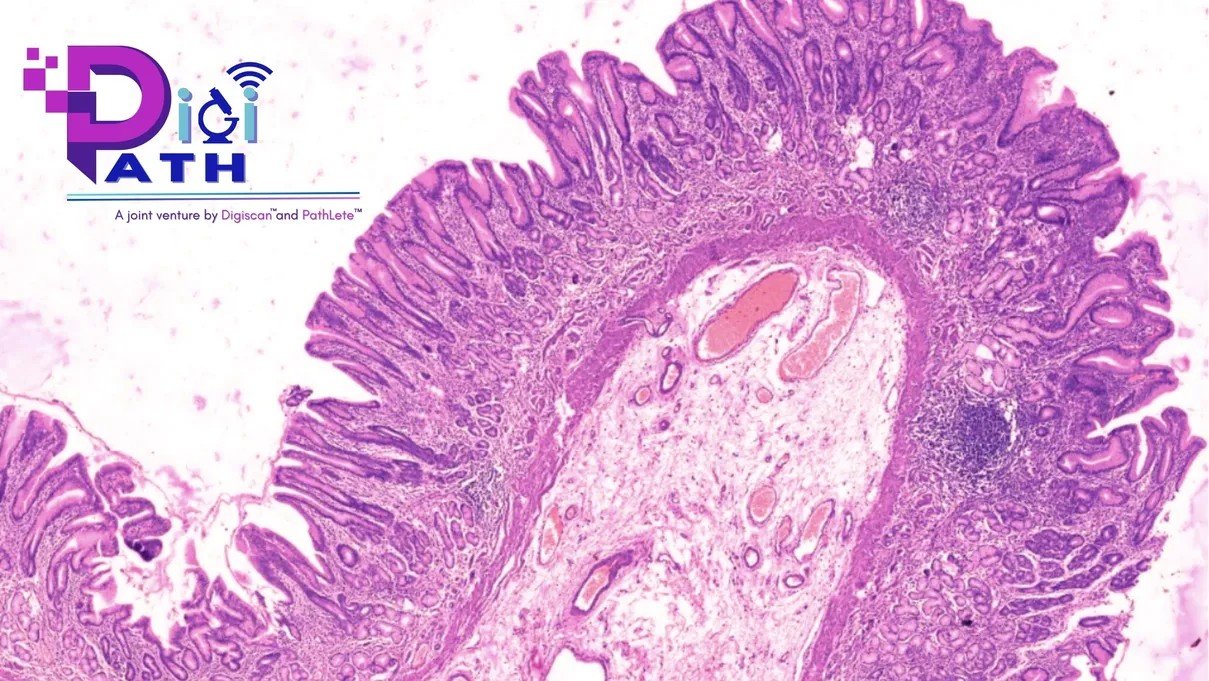

We are excited to unveil DigiPath, a state-of-the-art digital slide library, brought to you by a joint venture between DigiScan™ and PathLete™. This exceptional resource embarks on a transformative journey in diagnostic pathology, epitomizing the confluence of cutting-edge technology with deep-rooted expertise.

Comprehensive Slide Library: Virtually scanned slides with high-resolution images covering a spectrum of lesions across all systems.